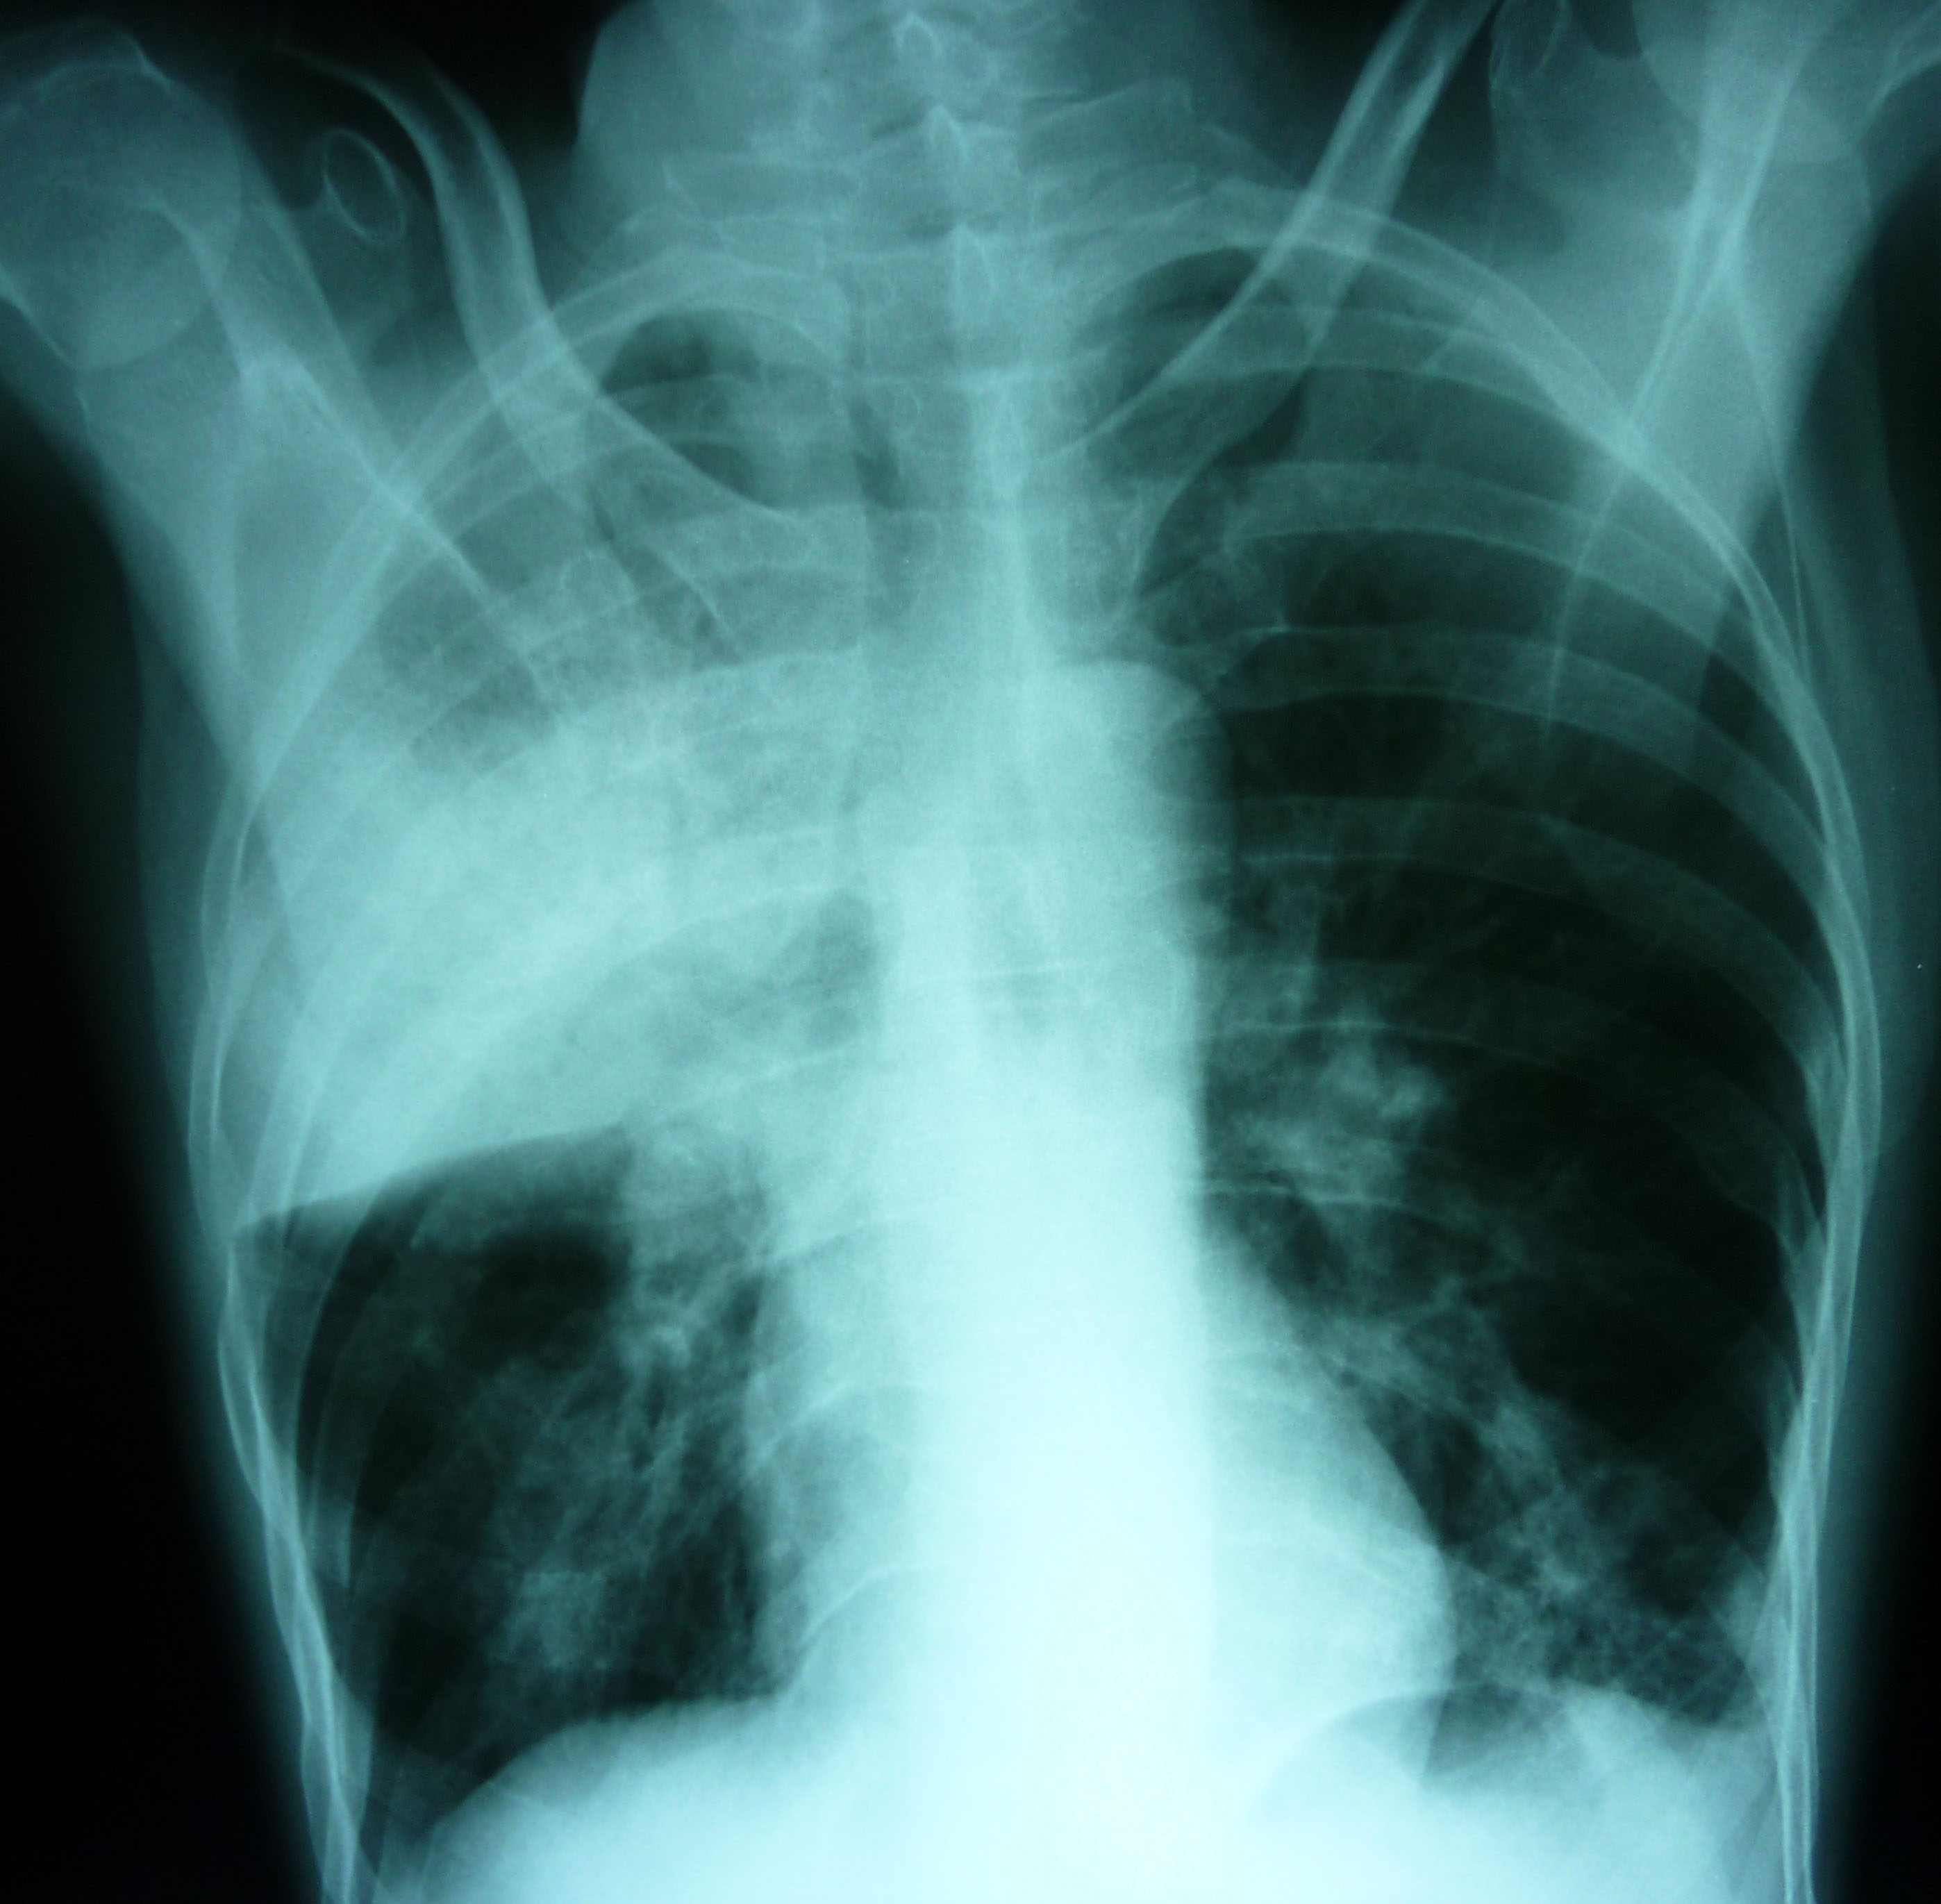

The World Health Organization estimates that one actively contagious person infects 10 to 15 people a year. Tuberculosis (TB) is an air-borne, infectious bacterial disease transmitted by bacilli when an infected person talks, sneezes, or coughs. It decays the lungs, and can spread to other organs. The appearance of tuberculosis often reflects the destruction of a country’s infrastructure through political and economic instability, deteriorating health systems and health conditions and, ultimately, through poverty.

HERE IS A MICROCOSM of all that goes wrong in a society: environmental, political, and economical. This instability leads to poverty, and poverty helps incubates the appearance of tuberculosis. Its new ‘ground zero’ for infection is Karakalpakstan, Uzbekistan, where the multi-drug resistant (MDR) tuberculosis rate is one of the highest in the world. Given these prevailing conditions, it is imperative that funds, programs and training, and first-line drugs be available to keep this MDR-TB epidemic from exploding throughout Uzbekistan and beyond its borders to the rest of the world.